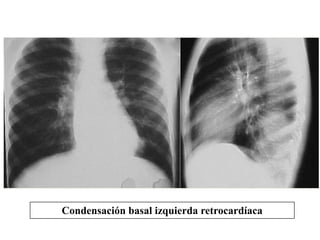

Hepatizacion pulmonar (consolidacion)

Condensación basal izquierda retrocardíaca